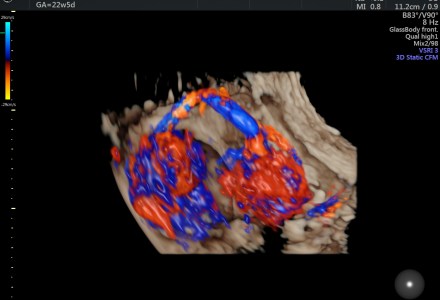

D.O.R.V.